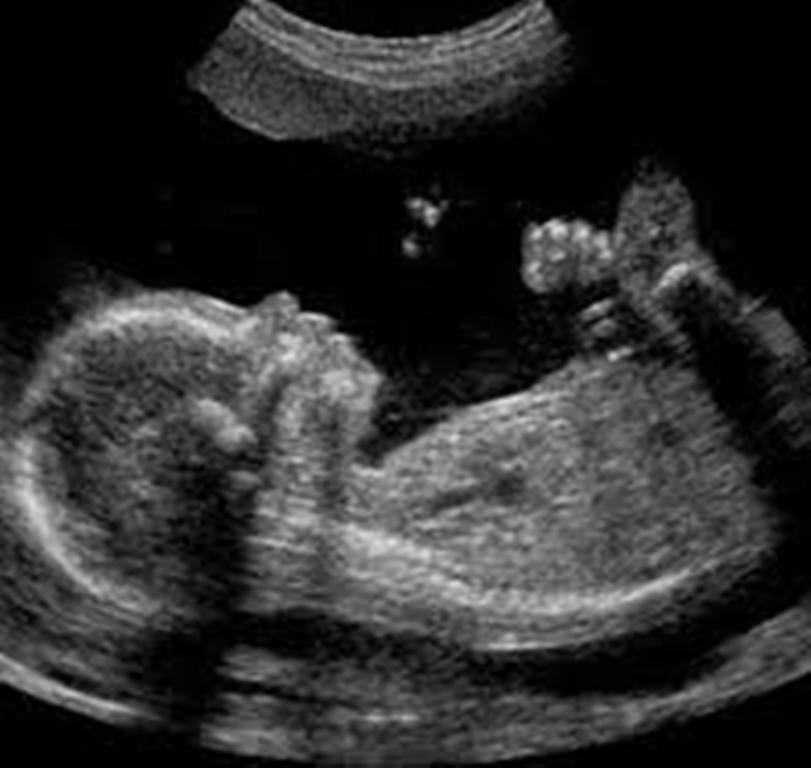

Kështu pas analizave të thelluara u bë zbulimi makabër, në barkun e 53-vjeçares, ishte një fetus, motra binjake e fëmijës së fundit, e cila ishte kalcifikuar brenda nënës.

Lidhur me këtë rast kanë nisur hetimet, ndërkohë që nga pikëpamja mjekësore cilësohet e çuditshme se si askush nuk ka arritur të pikasë praninë e një fetusi prej 8 centimetrash.

Mirëpo nga pikëpamja mjekësore ky fenomen quhet si ‘lithopedion’ dhe ka të bëjë me vdekjen e fetusit gjatë një shtatzënie jashtë mitre.

Në një rast të tillë fetusi vdes në bark dhe absorbohet bashkë me ambientin që e rrethon. /a.y/noa.al